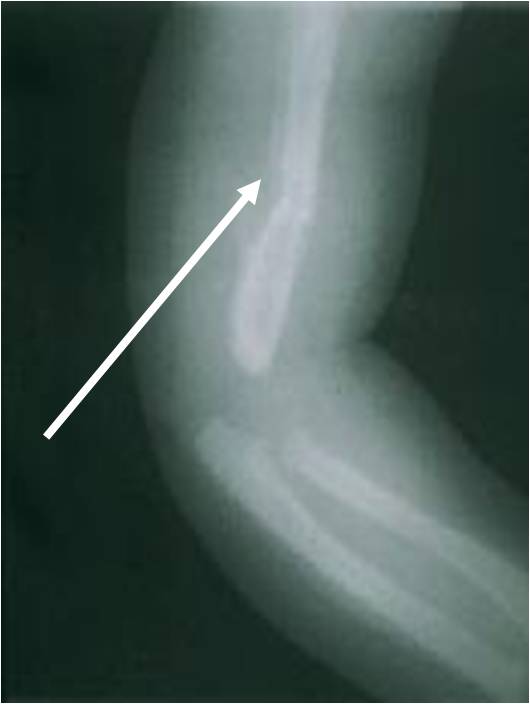

Paciente de 2 meses de edad que refirió el padre que se le resbaló, pero al hacer el Rx se ve una gran formación del callo que data de una semana antes, además la descripción del evento es inconsistente de acuerdo con el trauma recibido